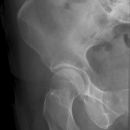

Hüftgelenk a.p.

Indikation

Cave: selten isoliert, meißt mit Luxation oder Azetabulum# kombiniert), Hüftgelenksluxation

Beurteilungskriterien

- CCD- Winkel (120-130°) Spongiosaarchitektur, Trajektorienverlauf im Schenkelhals (Cave: Bei nicht dislozierten SHF Diskontinuität der Trabekel oft einziges Frakturzeichen!)

- Shenton´sche Linie (Harmonischer Bogen aus kaudaler Schenkelhalskontur und der kranialen Zirkumferenz des For. obturatum)

- Gelenkstellung, Gelenkspaltweite (4-5mm nach medial, 3-4mm nach kranial), Luxation => Hüftkopf in ap und axialer Aufnahme in Azetabulum zentriert? Hüftkopfrundung?

- Azetabulumfraktur: vorderer und hinterer Pfannenrand, Pfannendachkontur, Köhlersche Tränenfigur, ggf. Zusatzaufnahmen (Ala- und Obturatoraufnahme), sowie CT

- medialer Azetabulumdachbogen (45° von der Hüftkopfmitte ausgehend nach vorne (!); Teil der lasttragenden Zone des Azetabulums, vgl. Obturatoraufnahme)

- Trochanter major et minor (Abriss, pertrochantäre #?)

- Weichteilzeichen (Fettstreifen medial des M.gluteus minimus zw. M.glutaeus minimus und medius, medial des M.iliopsoas; Konturschatten des M.obturatorius int.)